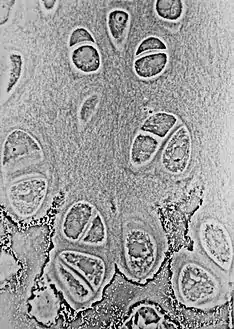

خلية غضروفية

الخلية الغضروفية (بالإنجليزية: Chondrocyte) وهي الخلية الوحيدة الموجودة في الغضروف السليم.[1][2][3] تنتج وتحافظ على المصفوفة الغضروفية التي تتكون أساسا من الكولاجين والبروتين سكري. على الرغم من استخدام كلمة أرومة غضروفية يكون شائع كوصف للخلية الغضروفية غير الناضجة، وهذا المصطلح غير دقيق لأن خلايا السلف الغضروفية (الخلايا الجذعية الوسيطة) يمكن أن تتفرق إلى أنواع متعددة من الخلايا بما في ذلك خلايا بانيات العظم.